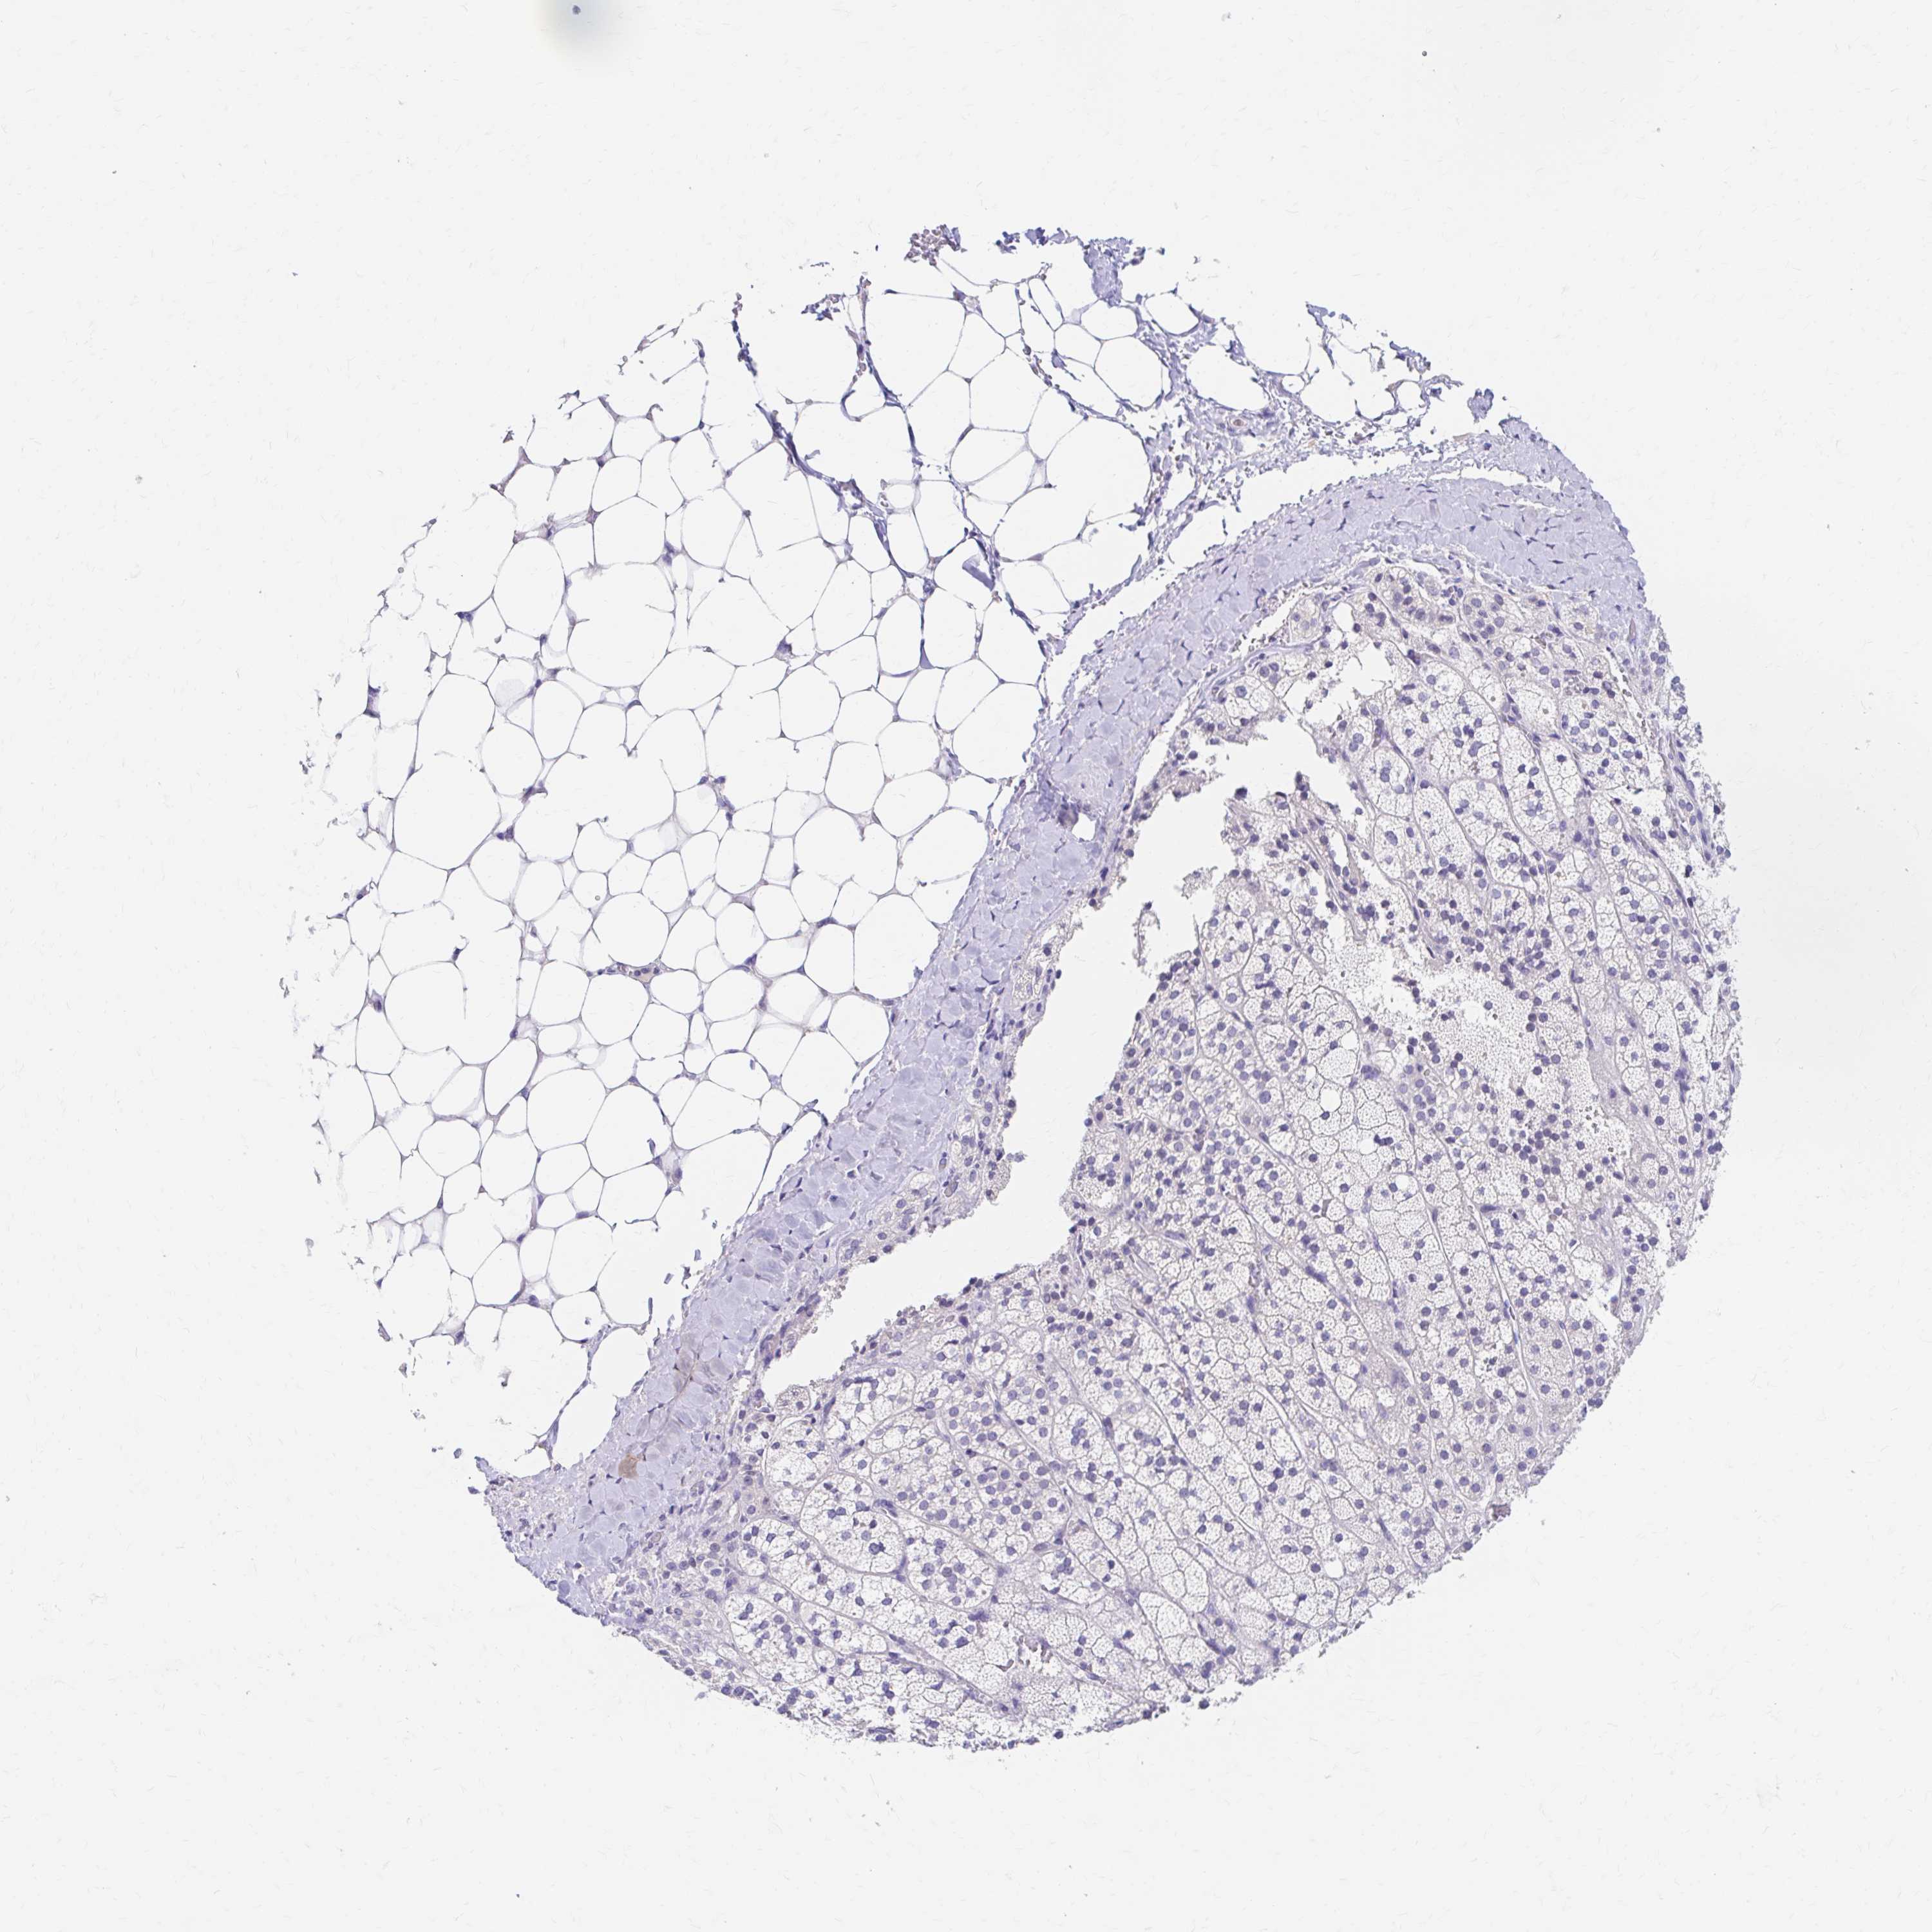

ADRENAL GLAND - Antibody stainingi

Antibody staining in the annotated cell types in the current human tissue is reported as not detected, low, medium, or high, based on conventional immunohistochemistry profiling in selected tissues. This score is based on the combination of the staining intensity and fraction of stained cells.

Each image is clickable and will lead to virtual microscopy that enables deeper exploration of all samples and also displays staining intensity scores, fraction scores and subcellular localization as well as patient and tissue information for each sample.

Antibody HPA012582Antibody CAB016087Antibody CAB032276

Glandular cells Not detectedNot detectedNot detected